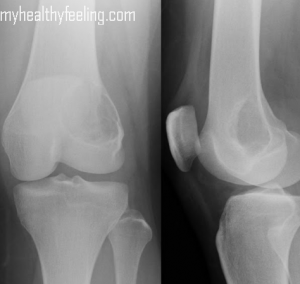

Knee pain pictures

Check out these knee pictures to get a better understanding of pain management